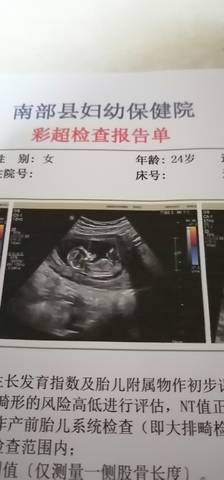

集美们 今天NT过了 帮我看看是个弟弟还是妹妹????谢谢啦

journal_insert_pic_1681381493journal_insert_pic_1681381523journal_insert_pic_1681381547journal_insert_pic_1681381567